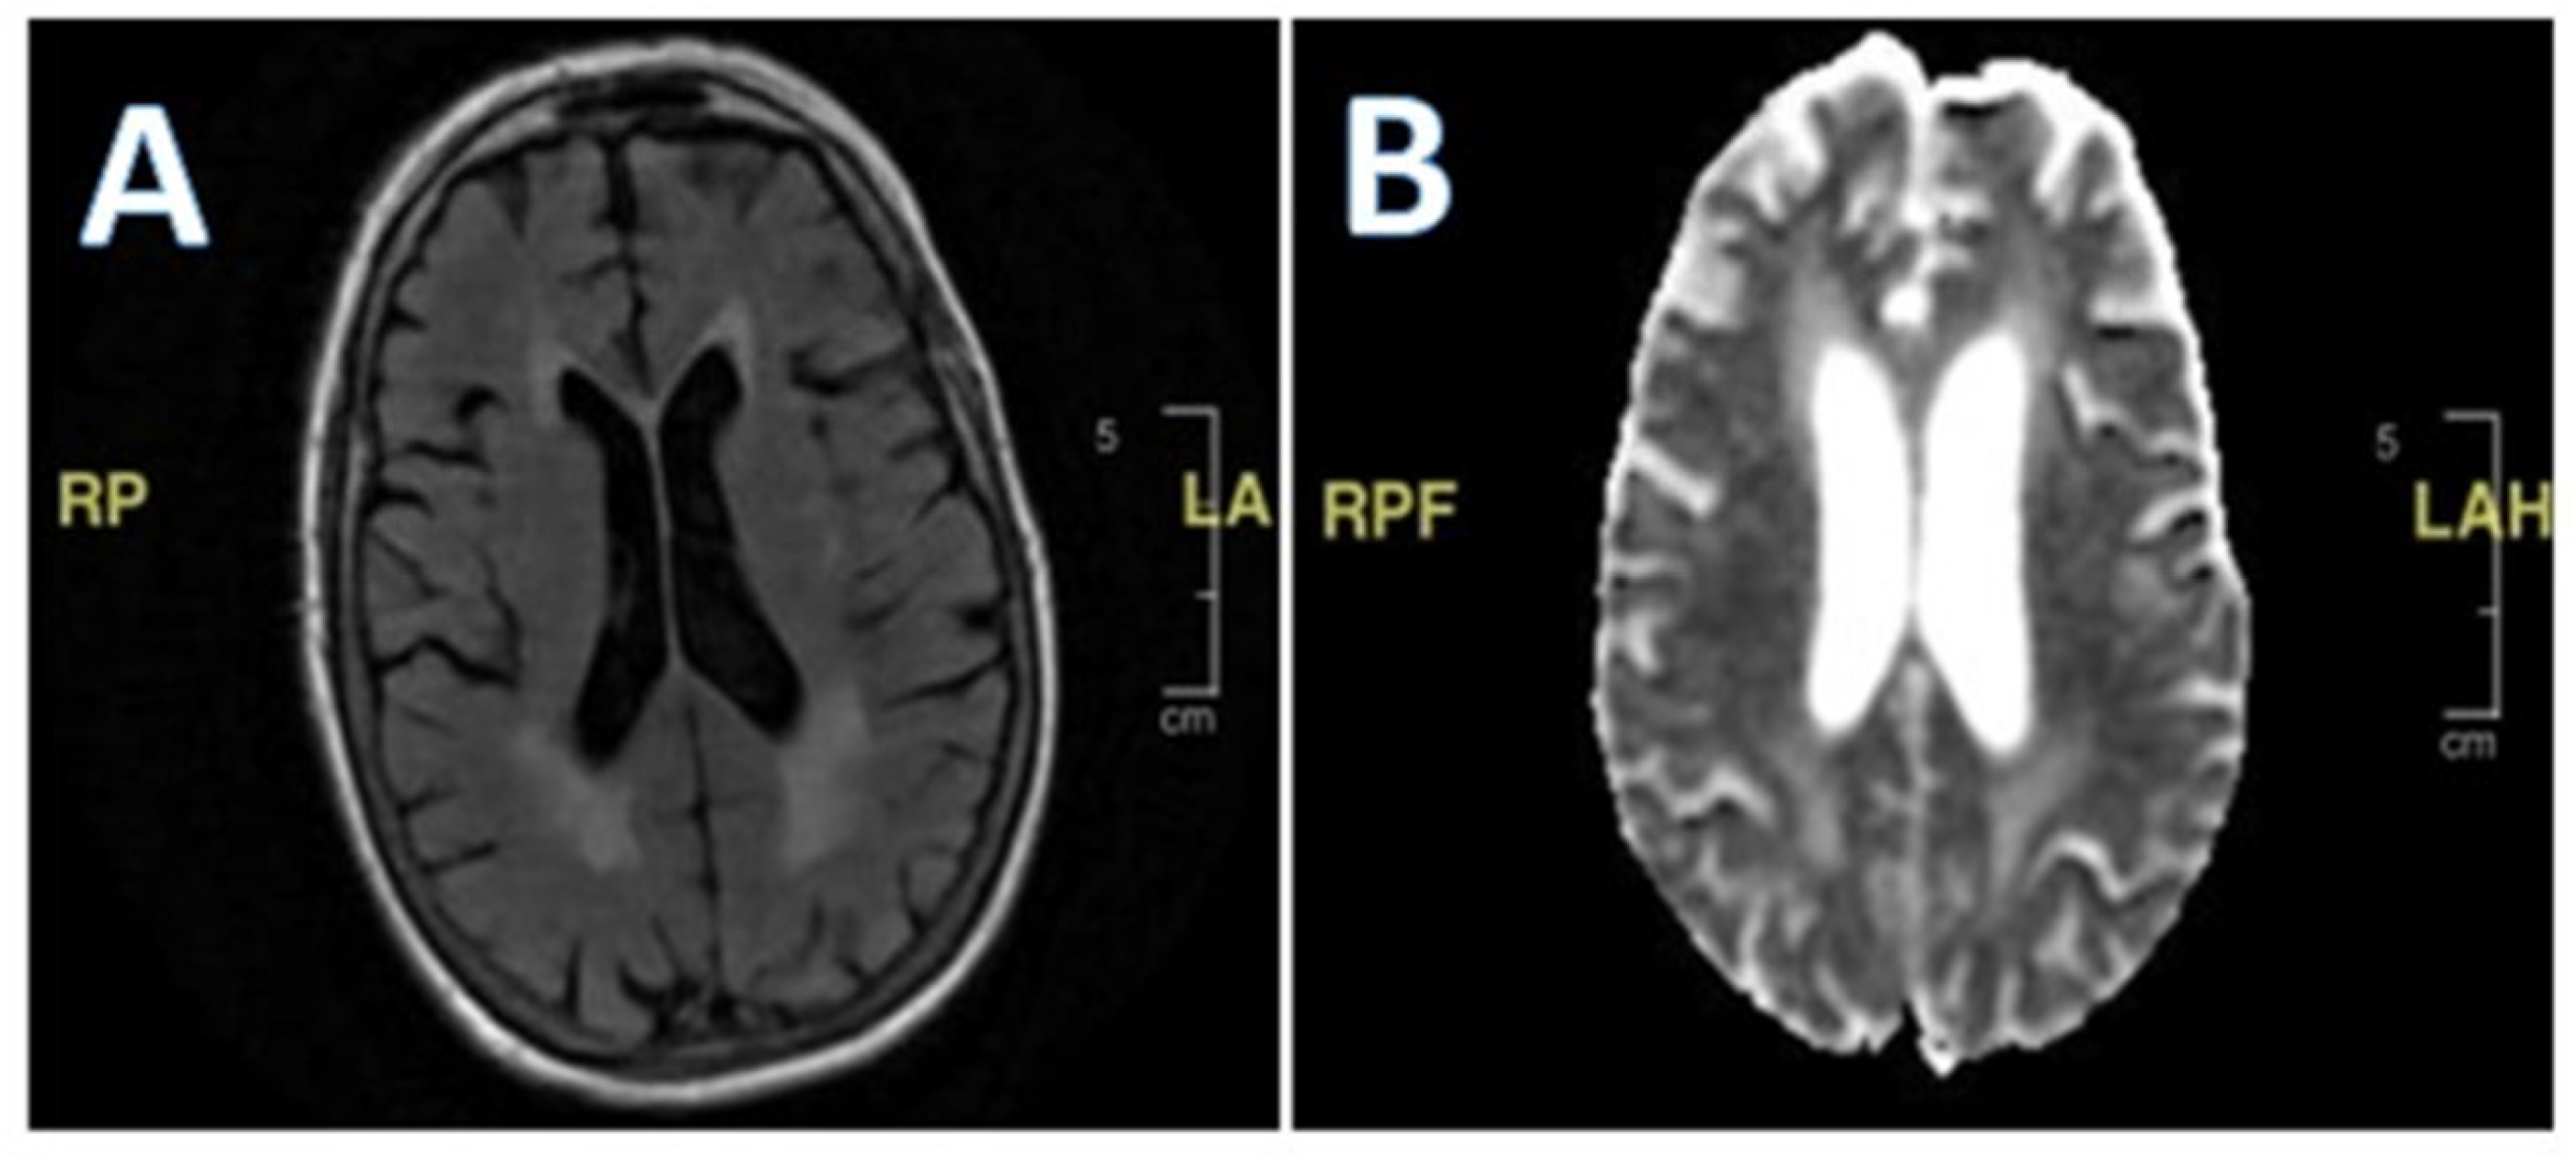

During the initial hospitalization, she was also evaluated for seven days of diplopia. She had both vertical and horizontal diplopia with mild vertiginous symptoms. Her physical examination then was remarkable for mild right-eye ptosis, subjective diplopia, left-sided facial weakness (left-sided facial droop), and decreased right hemi-body sensation to light touch associated with right lower-extremity weakness. Laboratory studies were non-diagnostic, including thyroid hormone function, vitamin B12, folate, inflammatory markers, and creatine phosphokinase. Radiological imaging, including a cerebral computed tomography scan and magnetic resonance imaging (MRI), showed no acute findings (Figure 1). She was discharged home with ophthalmologist follow-up, and the latter evaluation found no abnormality explaining her symptoms.

Figure 1. Brain magnetic resonance imaging (MRI). There is no mass effect, hemorrhage, edema, midline shift, or extra cerebral fluid collection. The ventricles and subarachnoid spaces are appropriate in size for the patient’s age.